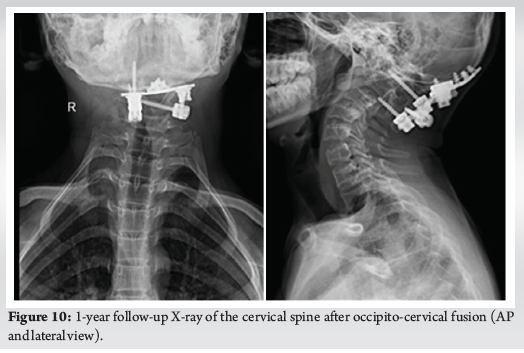

Atlanto-occipital Assimilation with Basilar Invagination and Atlanto-occipital Dislocation Treated by Occipitocervical Fixation: A Rare Case Report

Tushar Pisal , Sagar Gurnani , Kaman Kuity ………………………………p.53-57